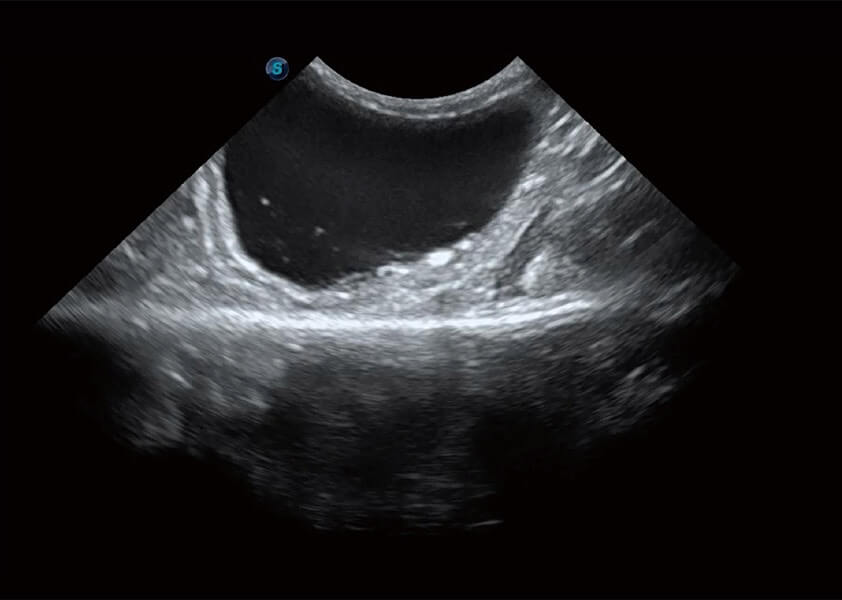

ProPet 60 作为一款高端台式动物超声设备,为动物医生的日常诊断提供了一系列贴合动物临床需求、解决临床实际问题的高级成像功能。凭借全系列高清探头,满足医生对腹部、心脏、生殖、浅表、肌骨等成像的所有需求,切实帮助您提升检查效率,提高诊断信心。

动物是人类最亲密的朋友和最值得信赖的伙伴。狗万官方网站也一直致力于探索动物专用的超声影像解决方案。 全新推出的ProPet系列,是狗万官方网站在动物超声影像智能化、专业化、精准化的一次跨越式革新。动物不能用言语来表述自己的不适,通过超声影像,ProPet系列搭建了动物医生与不同物种沟通的“桥梁”,为动物医生注入了“治愈之力”。